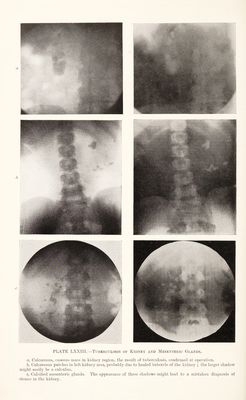

Radiography and radio-therapeutics / by Robert Knox.